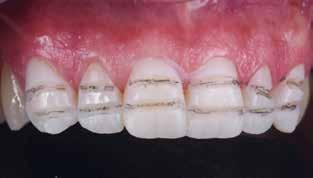

ESZTÉTIKUS, MINIMÁLINVAZÍV RESTAURÁCIÓ

MUNKAFOLYAMATTAL

Egy 42 éves férfi páciens jelentkezett rendelőnkben a mosolya megszépítésének a céljából.

A páciens tisztában volt a felső állcsont frontrégiójában elhelyezkedő fogainak és néhány hátsó fogának kopásával. Ez az állapot a dentin jelentős mértékű expozíciójához vezetett, amely nagyfokú érzékenységet és esztétikai problémát okozott a frontrégióban, különösen mosolygáskor (1. ábra). Emellett a fogak torlódása és Angle III. osztályú moláris viszony is látható volt, amely eltérést az okklúzióban, illetve III. osztályú kismetsző anomáliára és élharapásra való hajlamot eredményezett (2. ábra).

A páciens két-három évvel korábban egy másik klinikán fogászati kezelésen esett át, amely nem volt teljes körű, és az alsó molárisok, a jobb alsó második premoláris és a bal felső első premoláris kezelése befejezetlen maradt. A páciens kérése az volt, hogy a már elkészült restaurációkat, amennyiben azok még jó állapotban vannak, tartsuk meg.

Kezelés

Az első lépés az okklúzió vertikális dimenziójának (VDO, „vertical dimension of occlusion”) növelése volt okkluzális héjak felhelyezésével az abradált és erodált

fogakra, amelyek a következők voltak: 17-14, 2527, 34-es, 35ös és 44-es fogak. A megnövelt VDO-ról digitális lenyomatot vettünk a DEXIS IS 3800 W intraorális szkenner segítségével (Dental Imaging Technologies Corp.), az állcsontok centrális relációja közben, amelyet egy hátsó okkluzális rögzítővel stabilizáltunk (3. ábra).

A restaurációkat az exocad szoftverrel terveztük (4. ábra), és a lítium-diszilikát anyagot választottuk az elkészítésükhöz (5. ábra). A restaurációkat adhezív módon ragasztottuk be.

A VDO növelése után a páciens okklúziója a frontrégióban ideális volt az elülső vezetés helyreállításához, ami miatt szükségessé vált a páciens orthodonciai kezelése is (6. ábra).

A fogszabályozó kezelés befejezése után az alsó metszőfogak incizális éleit direkt módon, kompozittal állítottuk helyre (7. ábra).

Ezt követően elkészült a frontrégió esztétikai wax-upja, az esztétikai restauráció végleges validálása és a felső koronák minimálinvazív preparálásának támogatása érdekében (8. ábra). A végső preparálást a mock-up (9. ábra) segítségével végeztük, amely nagyrészt az aproximális területekre korlátozódott (10. ábra). Ezt követően az elülső koronákról fonalazást követően egy végső digitális lenyomatot vettünk (11. ábra).

A digitális tervezésnél a monolitikus restauráción a bukkális felszín alsó felét mérsékelten redukáltuk, hogy a lehető legjobb esztétikai eredmény elérése érdekében lehetővé tegyük a porcelán rétegzését (12-13. ábra). Végül a végleges restaurációkat (14. ábra) adhezív módon ragasztottuk be, a kofferdam izolálás mellett (15. ábra). A cementrögzítést követően néhány héttel kontrollvizsgálatot végeztünk (16-17. ábra).